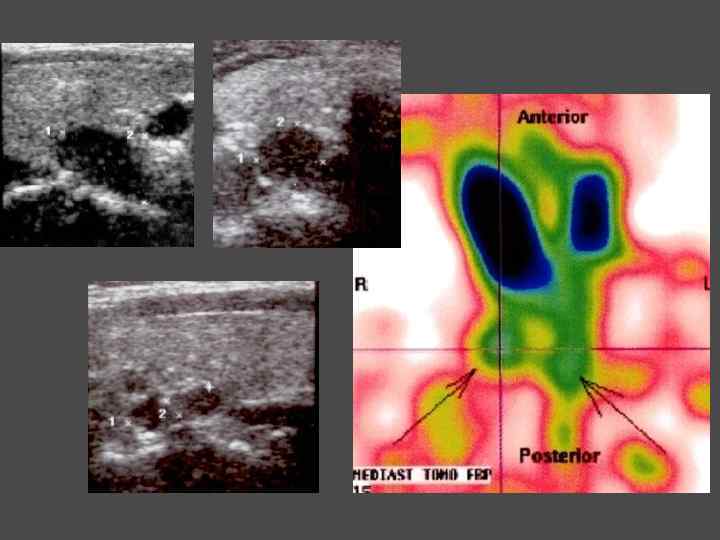

МЕТОДЫ ИССЛЕДОВАНИЯ ► Определения уровня кальция крови, паратгормона ► Сцинтиграфия паращитовидных желез с Тс99 ► УЗИ ► ПТАБ ► КТ, МРТ ► Денситометрия